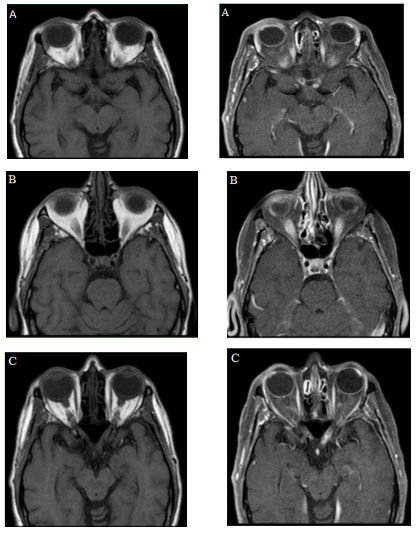

During hospitalization, the following were performed: hemogram, creatinine, BUN, electrolytes without abnormalities, extended examination with infectious panel (serology, hepatitis B and C, and HIV), immune panel: Antinuclear antibody (ANA) 1:160 speckled pattern (serum), anti-dsDNA, Anti-SCL-70, P-Anca, and C- Anca, myeloperoxidase, and including ANA and flow cytometry in CSF were normal. Performed a simple orbital resonance with a contrast medium (Figure 2) that showed an abnormality in the signal and enhancement of the optic chiasm, optic radiations and optic nerves bilaterally, conclusive findings of bilateral longitudinally extensive optic neuritis.

Figure 2 Simple MRI of orbits and with a medium of contrast. Simple and contrasted T1 images, (A, B, and C) evidencing signal alteration and enhancement with the medium of contrast, of the optic chiasm, optic radiations, and optic nerves, characteristic findings of longitudinally extensive bilateral optic neuritis.